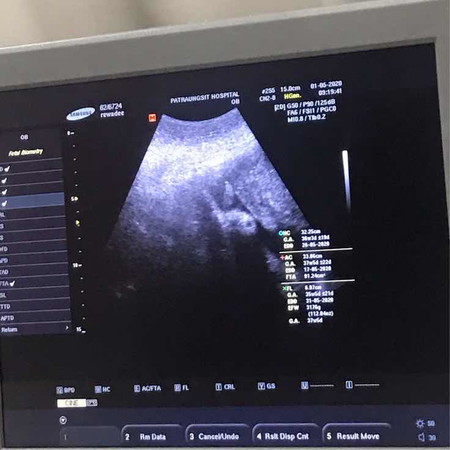

กำหนดคลอด24 พค. แต่ความดันขึ้น150-160 วัดสิบกว่ารอบก็ไม่ลงโดนแอดมิดดูอาการ หมอสั่งยาความดันมาให้กินถ้าไม่ลง โดนผ่าฉุกเฉิน ไม่งั้นจะอันตรายทั้งแม่และลูก ตอนนั้นอายุครรภ์แค่36+5 หมอยังไม่อยากให้ผ่า อยากยื้อให้ครบ38w ถ้ายื้อได้ คนเป็นแม่ได้แต่ห่วงลูก ต่างๆนาๆ แต่พอคุณหมอมาดูซาวด์ลูก จากที่แม่ร้องไห้กลายเป็นหัวเราะและมีกำลังใจขึ้นมา ลูกชู2นิ้ว บอกแม่สู้ๆนะ หมอยังยิ้มและหัวเราะตาม คุณหมอพูดว่าน้องบอกให้คุณแม่สู้ๆน้า เราคุยกับลูกในท้องทุกวันตั้งแต่ตั้งครรภ์ จะกินข้าวก็เรียก ไปข้างนอกก็บอกลูกไปด้วยกันนะ ลูกคงรับรู้ในสิ่งที่เราสื่อสาร อย่าอายที่จะคุยกับลูกในท้อง เพราะเชื่อว่าเขารับรู้ความรู้สึกเรา? เราจะสู้ไปด้วยกันนะลูก ขอให้หนูแข็งแรงและปลอดภัยดวงใจของแม่ ✌?❤️ ปล.หมอนัดผ่า 14พค.นี้แล้วค่ะ เป็นกำลังใจให้พวกเราด้วยนะคะ??